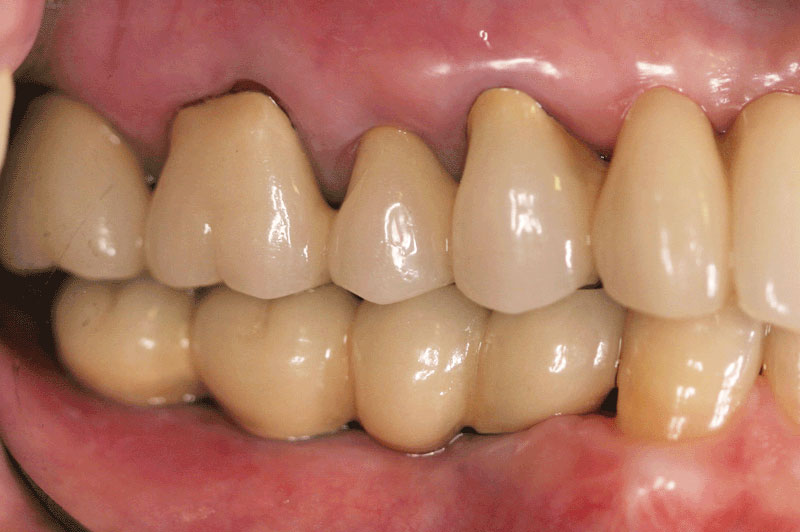

があります。それぞれ利点・欠点がありますが、ブリッジのように土台の歯を削る必要がなく、入れ歯のように取り外しのわずらわしさがなく、自分の歯のように治療できるのがインプラント治療です。

CASE 2 下の奥歯がない方